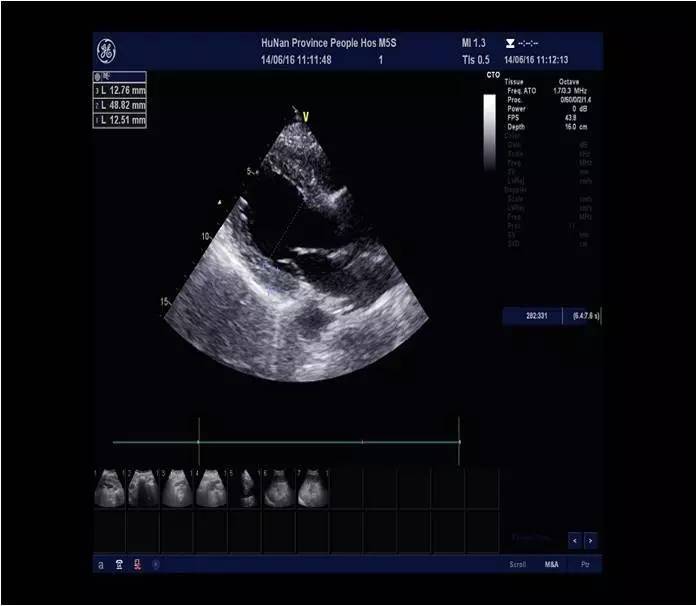

AO窦部:42mm AAO:38mmLA:31mm LV:DM:48mm SM:35mmPA:22mm RA:26mm RV:26mm IVS:14mm LVPW:12mm

心功能:EF:51%;FS:27%

a.主动脉窦部及升主动脉内径增宽

b.左室壁增厚、运动不协调

c.二尖瓣、三尖瓣轻度返流

d.主动脉瓣轻-中度返流

e.左室舒张功能减退、收缩功能测值偏低

2.本例患者心梗40天后复查,心脏超声LVEF 51%,LVDM 48mm,心功能Ⅱ级,可不植入ICD。